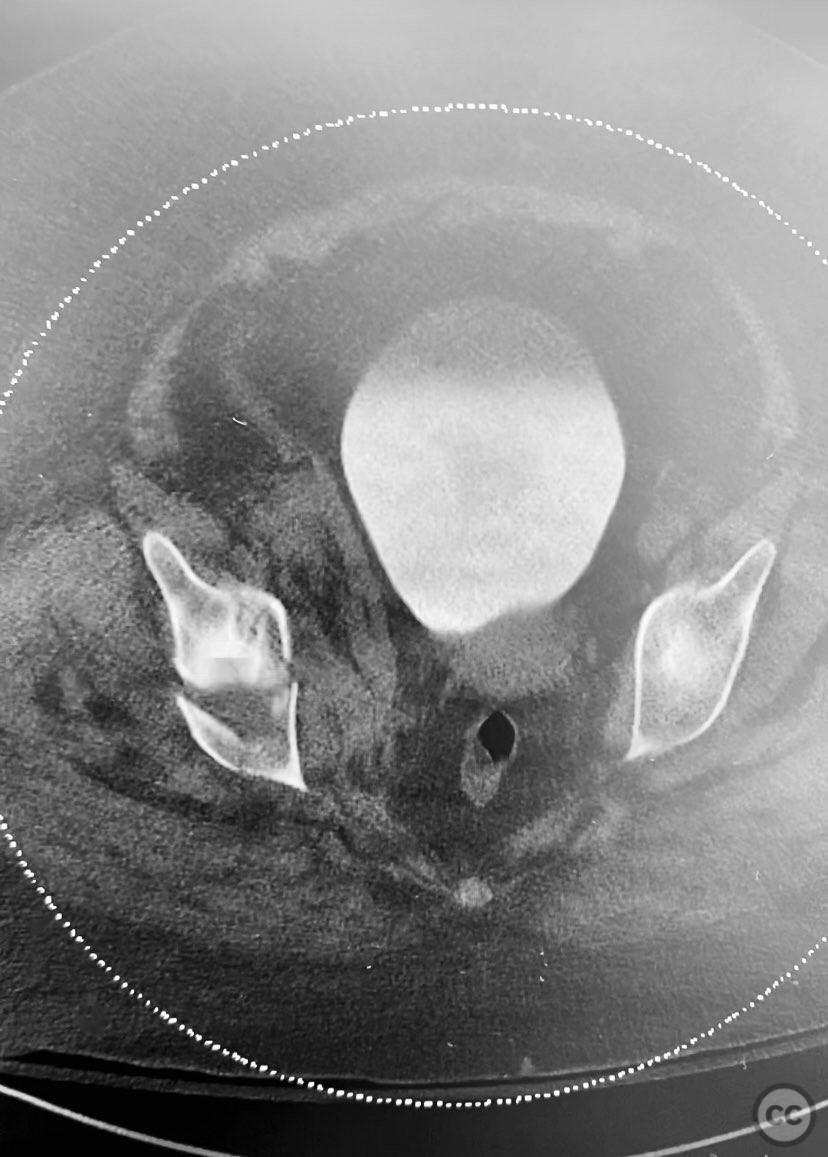

acetabulum fracture

türkiye, Turkey

Pelvis - AO/OTA 6x